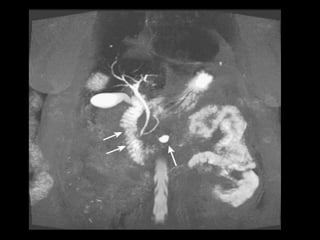

T1: tecido pancreático ao redor da segunda porção

CPRM: compressão extrínseca